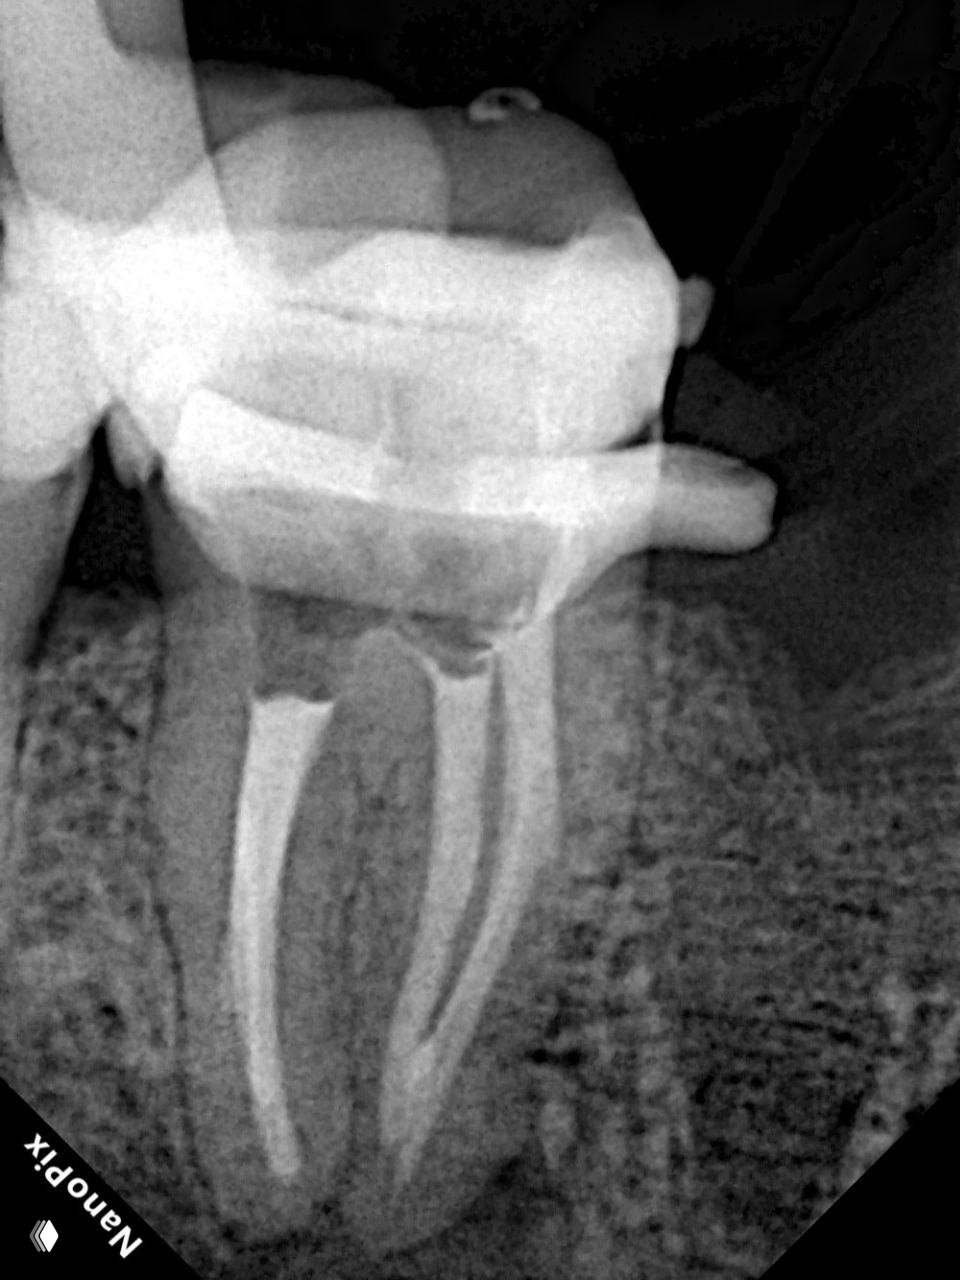

Контрольный осмотр через 6 месяцев показал отсутствие клинической симптоматики и уменьшение очага. То есть у нас наблюдается стадия активного заживления и можно покрывать этот зуб постоянной коронкой ✅

- 🔹 Во второе посещение работа шла по чёткому плану. Сначала закрыли перфорацию быстротвердеющим Рутдентом. После этого дистальный канал обтурировали по методике Шилдера, а мезиальные каналы запломбировали методом вертикальной компакции непрерывной волной.